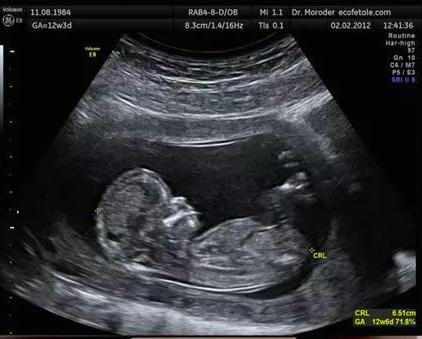

双顶径,也就是胎儿的头围数值,是指胎儿头部的直径,在医学上,把胎儿头部左右两侧之间最宽部位的长度,称为双顶径。医生会用这项数值来观察胎儿的发育情况,判断产妇临产时,是否可以顺产。

为什么双顶径超过10厘米就不能顺产了呢?我们知道,顺产,就是胎儿自然分娩,能够自主的通过产妇的产道,而产道最狭小的地方,就是产妇的骨盆口。正常的女性的骨盆,骨盆中最窄的一条经线宽度大约为10厘米。也就是说,未来胎儿要从子宫出来,胎头和身子,不能超过这个长度,否则,肯定会出现难产。

所以说,如果胎儿的双顶径超过了10厘米,难以通过妈妈的骨盆,顺产就难了。因为胎儿的头围已经大于骨盆出口横径了。更何况,有些女性的骨盆宽度还小于10厘米。在临床上,我们所说的头盆不称,就是这意思。所以,即将临产的孕妇,把胎儿的头围控制在10厘米以内,是很重要的。这就需要,在孕晚期,控制饮食,还有就是妊娠糖尿病的产妇,一定要控制好血糖,否则,出现巨大儿,头盆不称,是很难顺产的。